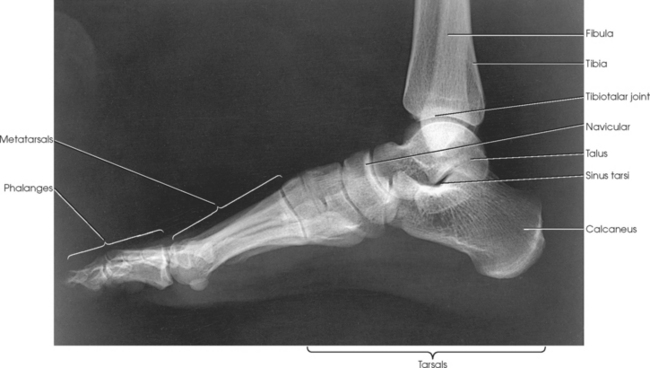

Structures shown: The resulting image shows a true lateral projection of the lower third of the tibia and fibula; the ankle joint; and the tarsals, including the base of the fifth metatarsal (Figs. 6-94 and 6-95).

Fig. 6-94 Bones shown on lateral ankle. Including base of fifth metatarsal on lateral ankle projection can identify Jones fracture if present.